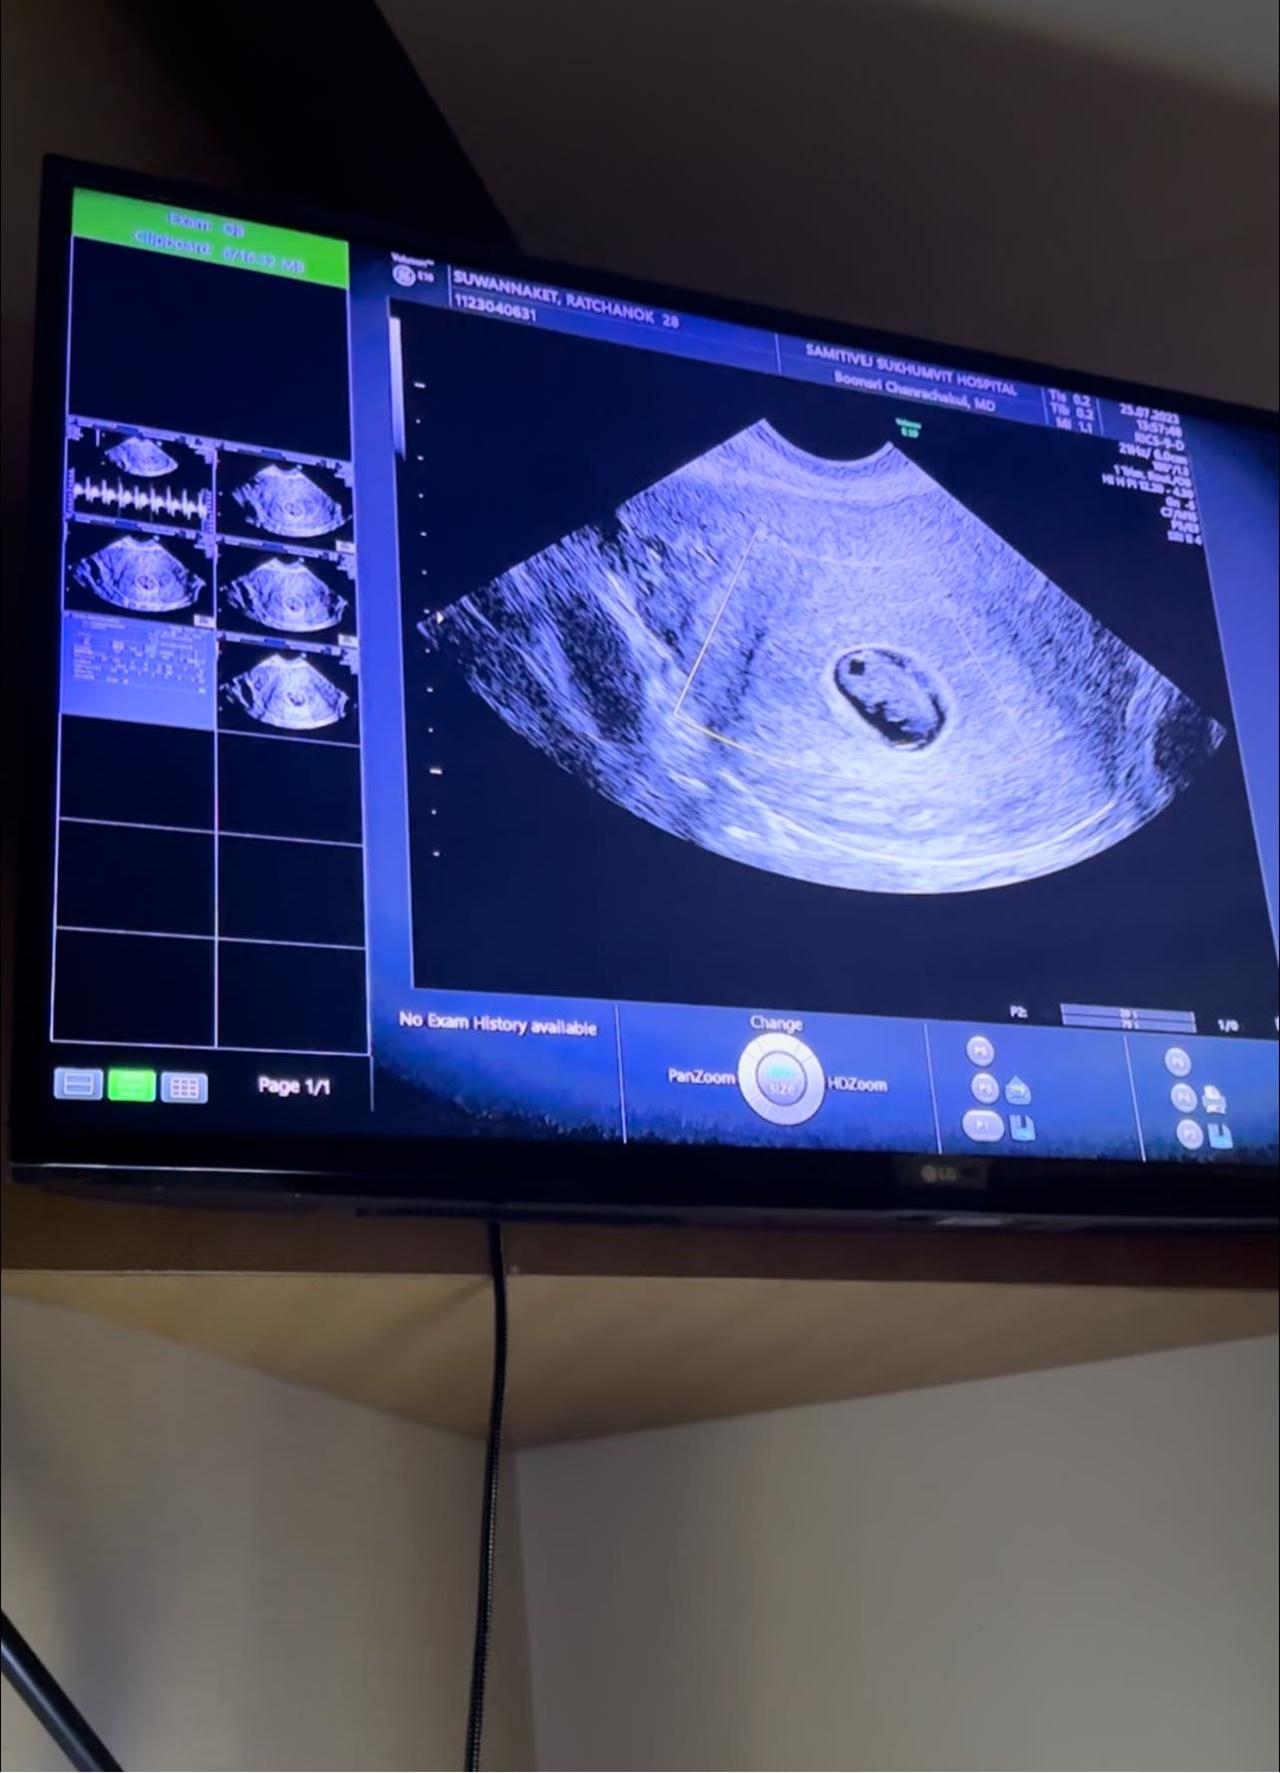

ก่อนที่ล่าสุดเมื่อวันที่ 31 ก.ค. ที่ผ่านมา เจนนี่ จะออกมาเปิดเผยข่าวเศร้า ได้สูญเสียลูกในท้องไปแล้ว เพราะร่างกายของน้องไม่สมบูรณ์ "ผลอัลตราซาวนด์วันนี้ คุณหมอไม่เจอหัวใจน้องแล้วนะคะ เนื่องจากร่างกายของน้องไม่สมบูรณ์ค่ะ โชคดีนะตัวเล็ก ไว้มาใหม่นะลูก แม่จะรอนะ"

จนกระทั่งวันนี้ที่เจนนี่ได้ทำการอัลตราซาวนด์ครั้งที่สอง ปรากฏว่าป้าหมอไม่เจอหัวใจของน้องแล้ว (ป้าหมอพูดไม่ทันจบ ป๊ายิวก็ร้องไห้แล้วเดินออกไปจากห้องตรวจ) มดลูกของเจนนี่ไม่มีแผล ไม่มีอาการผิดปกติ แต่สาเหตุมาจากน้องไม่สมบูรณ์